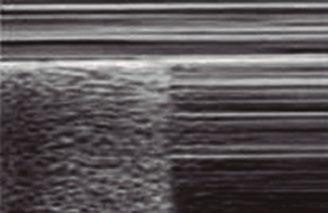

Utilidad clínica de la ecografía pulmonar y cardiaca en urgencias